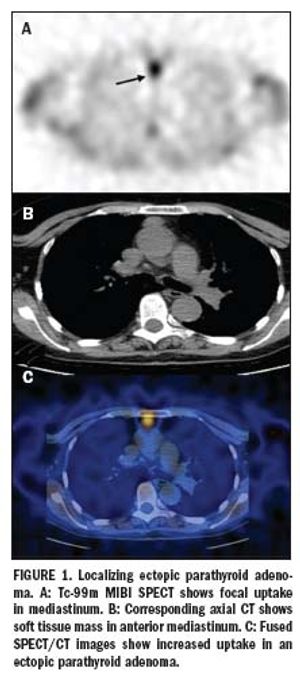

Multislice SPECT/CT gains wider clinical acceptance

ByGopinath Gnanasegaran, MD,Kathryn Adamson, MSc

Multimodality imaging is rapidly becoming an essential tool, particularly in oncology, where many publications have focused on a role for PET/CT.